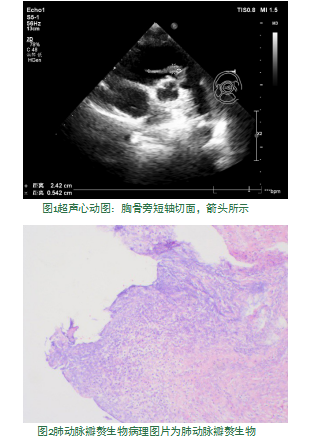

患儿李xx,女,7岁,因“检查发现室间隔缺损6+年”于2018年7月13日入住我院心胸外科,查体:胸骨左缘第三肋间隙可闻及收缩期吹风样杂音。超声心动图提示先天性心脏病:室间隔缺损(干下型),左向右分流。于2018年07月18日行体外循环下室间隔缺损修补术,术后4天恢复可,复查血常规、胸片无明显异常,办理出院[1-2]。术后7天患儿无明显诱因反复出现发热,最高体温达39.2℃,伴有畏寒,活动后气促、乏力,手术切口疼痛,于我院就诊,血常规示:WBC:12.95×10E9/L,GRI:83.3%,HGB:77g/L。心脏彩超示:肺动脉瓣上团状及运动的条索状强回声,考虑感染性赘生物(肺动脉瓣增厚、毛糙,瓣上可见团状强回声,大小约11.0×8.1 mm,并可见条索状强回声于瓣口随瓣膜运动来回摆动,长约24.2 mm,厚约5.4 mm,瓣口前向血流速度未见明显增快,瓣下可探及少量反流血流信号)。再次入住于我院心胸外科,查体:生命体征平稳,部分手术切口愈合欠佳,可见少许黄色分泌物,手术切口周围轻压痛,余查体未见明显异常;心律齐,胸骨左缘第二肋间隙可闻及收缩期杂音,余瓣膜听诊区未闻及病理性心杂音。诊断为感染性心内膜炎,给予抗感染、补液等对症治疗,血沉:37 mm/h,C-反应蛋白:135 mg/L,降钙素原:2.19 ng/mL,血浆D-二聚体:10.25 Ug/mL,血培养提示:金黄色葡萄球菌。因患儿病情进一步加重,出现呼吸困难,氧饱和度进行性下降,并转入ICU行呼吸机辅助呼吸等对症处理。床旁超声提示肺动脉瓣上赘生物仍然存在(肺动脉瓣上可见团状等回声,大小约18.0×14.0 mm),且不能排除赘生物脱落至肺动脉栓塞,手术探查指针明确,行体外循环下心内赘生物清除+肺动脉瓣成形+心包纵膈引流术(术中见:肺动脉瓣后瓣大量赘生物形成,瓣叶结构破坏明显)。病检回示:“肺动脉瓣赘生物”镜下由血小板、中性粒细胞、红细胞及细菌菌落组成。根据药敏加强抗感染治疗后患儿恢复情况佳,无发热,切口愈合可。复查血常规、细菌感染指标、胸片、心脏彩超

(2018年08月30日:肺动脉瓣右后瓣回声增强,瓣膜活动正常,开放未见明显受限,瓣口血流速度约1.4 m/s,PG:7.0mmHg,瓣下可探及少量反流血流信号,反流面积约3平方厘米)等未见明显异常,办理出院。